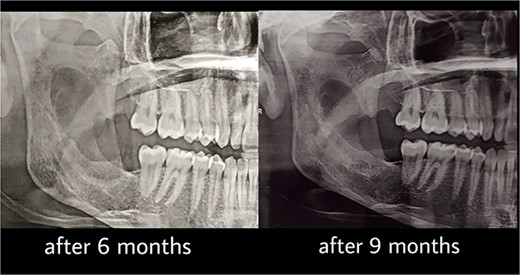

Under general anesthesia, an incision was made around the fistula to remove the overlying mucosa and expose the lesion. A 1 cm size window was made into the cyst cavity (Fig. 3). The cyst lining was sutured to surrounding mucosa. The cavity was kept open using a povidone iodine-saturated gauze, and it was replaced every 2 weeks. Follow-up radiograph (OPG) was recommended after 3, 6, 9 and 12 months (Figs 4 and 5).

Marsupialization procedure: exposure of the cystic cavity, 1 cm size window was made into the cyst cavity.